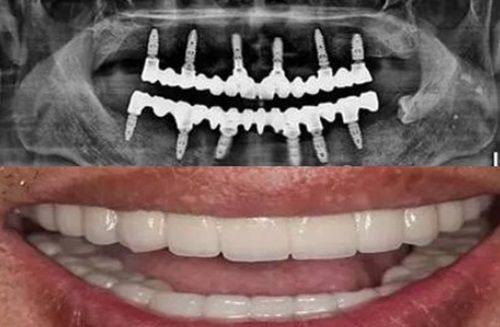

若为牙性问题(如牙列拥挤、牙性地包天、门牙外凸):可根据自身需求和预算选择多种矫正方式,比如性价比高的金属托槽、美观度出色的隐形牙套(隐适美、时代天使等)、兼顾美观与成效的半隐形陶瓷托槽等,这些方式的矫正成效都十分明确,能精细调整牙齿位置,解决牙性畸形问题。

若为骨性问题(如骨性地包天、骨性偏颌):30岁处于正颌手术黄金年龄段(23-35岁),此时颌骨发育完全定型,身体素质较好,治疗配合度佳,可通过“正畸+正颌联合治疗”完全改善骨性畸形。这种联合治疗方式能从骨骼层面解决根本问题,相较于单纯正畸,成效更完全、更稳定,能有效改善面部不对称、咬合重度错位等骨性问题。